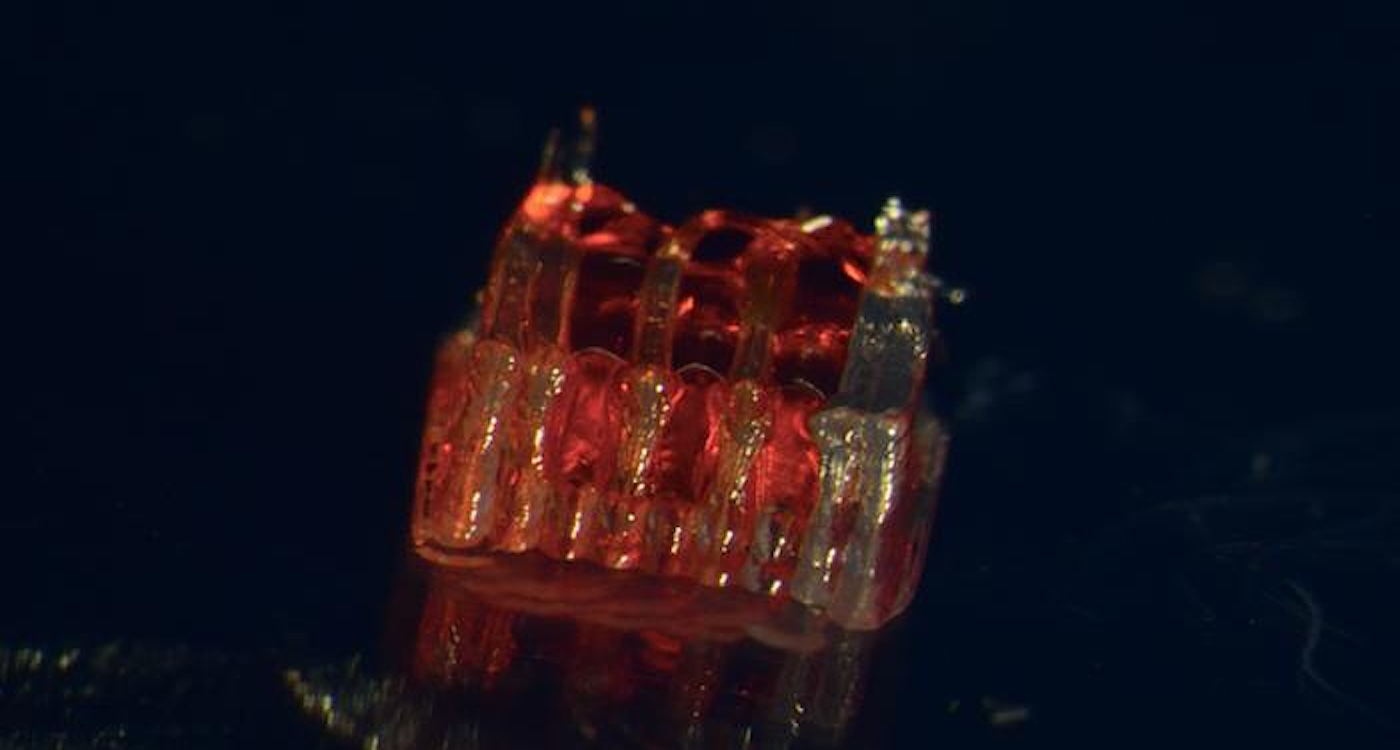

A breakthrough in stem cell biology has been 3D-printed in Minnesota—and the lab results show promise for spinal cord injury recovery, and even reversal. A research team at the University of Minnesota Twin Cities demonstrated a groundbreaking process that combines 3D printing, stem cell biology, and lab-grown tissues to provide spinal cord injury recovery. Currently […]

Injured Spinal Cords Repaired With Breakthrough 3D-printed ‘Scaffolding’–Team Regrows Nerves in Rats